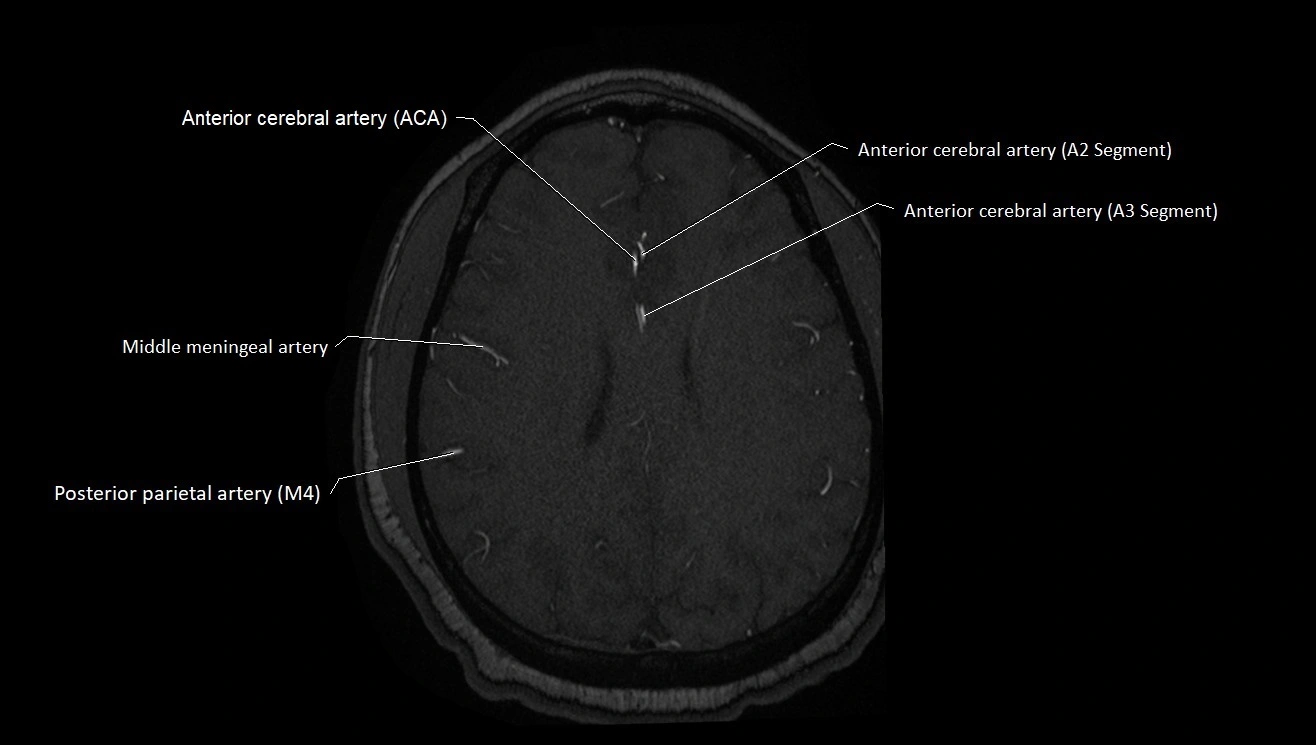

MRI images

image